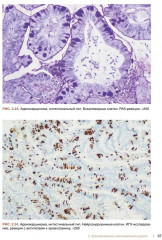

💳 Оплатить за товар можно при получении 🇰🇿 Есть бесплатная доставка по Казахстану от 1 дня 🎁 Копите бонусы с каждой покупки Настоящее руководство-атлас посвящено патоморфологической диагностике опухолей полости носа и носоглотки. Несомненным достоинством книги является систематизированное, лаконичное и вместе с тем весьма информативное изложение текстового материала (клинико-эпидемиологическая картина, морфологическая характеристика, дифференциально-диагностический ряд, необходимые дополнительные методы исследования), а так-же более 170 цветных микрофотографий наблюдений из собственной клинической практики с подробными подписями. Наряду с опухолями в книге представлен раздел наиболее часто встречающихся неопухолевых процессов синоназального тракта, необходимых для дифференциального диагноза. Руководство-атлас предлагает структурированный подход с унифицированным изложением современных данных о клинических и морфологических особенностях доброкачественных и злокачественных опухолей носа и носоглотки. |